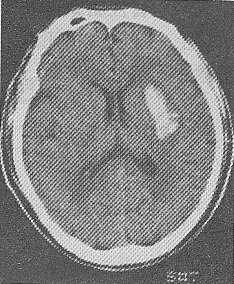

3.患者,男性,60岁。晨睡醒后左侧肢体无力,刷牙时无法拿杯,有糖尿病和高血压病史无心脏病史,半天后急诊。查体:左侧肢体肌力3级,腱反射高于右侧,左侧Babinski征阳性。左侧肢体痛温觉减退。脑CT见图示:可能的诊断为

正确答案:D 解题思路:试题难度:中,本题考查目的是综合临床资料和CT图像作出脑血管的诊断。从上题的脑缺血性卒中与脑出血性卒中的鉴别要点表中很容易得出标准答案D脑血栓形成。短暂性脑缺血发作的体征一般1~2小时恢复,而且以单肢瘫等局限体征为多见。CT图像上一般没有梗死灶。脑栓塞一般在活动状态下,数秒钟即出现明显脑症状,大多数患者有房颤等栓塞灶的来源。这些均与本例不符合,故缺血后卒中以脑血栓形成为正确答案。

4.患者,男性,52岁。清晨锻炼时觉头痛,左侧肢体麻木和乏力,有高血压病史,半天后急诊。查体:嗜睡,右侧肢体肌力3级,腱反射高于左侧,右侧Babinski征阳性。脑CT见图示:可能诊断为

正确答案:B 解题思路:试题难度:中,本题考查目的是综合临床资料和CT图像作出脑血管病的诊断。本病例为急性起病的脑血管疾病。脑血管病分为缺血性卒中和出血性卒中。脑血栓形成、短暂脑缺血发作、脑栓塞均为缺血性卒中范畴;高血压性脑出血为出血性卒中;根据脑缺血性卒中和脑出血性卒中的鉴别诊断表(下表),可以得出B,高血压性脑出血为正确答案。脑转移癌起病较慢,而且CT的病灶周围有大片水肿,为迷惑答案。